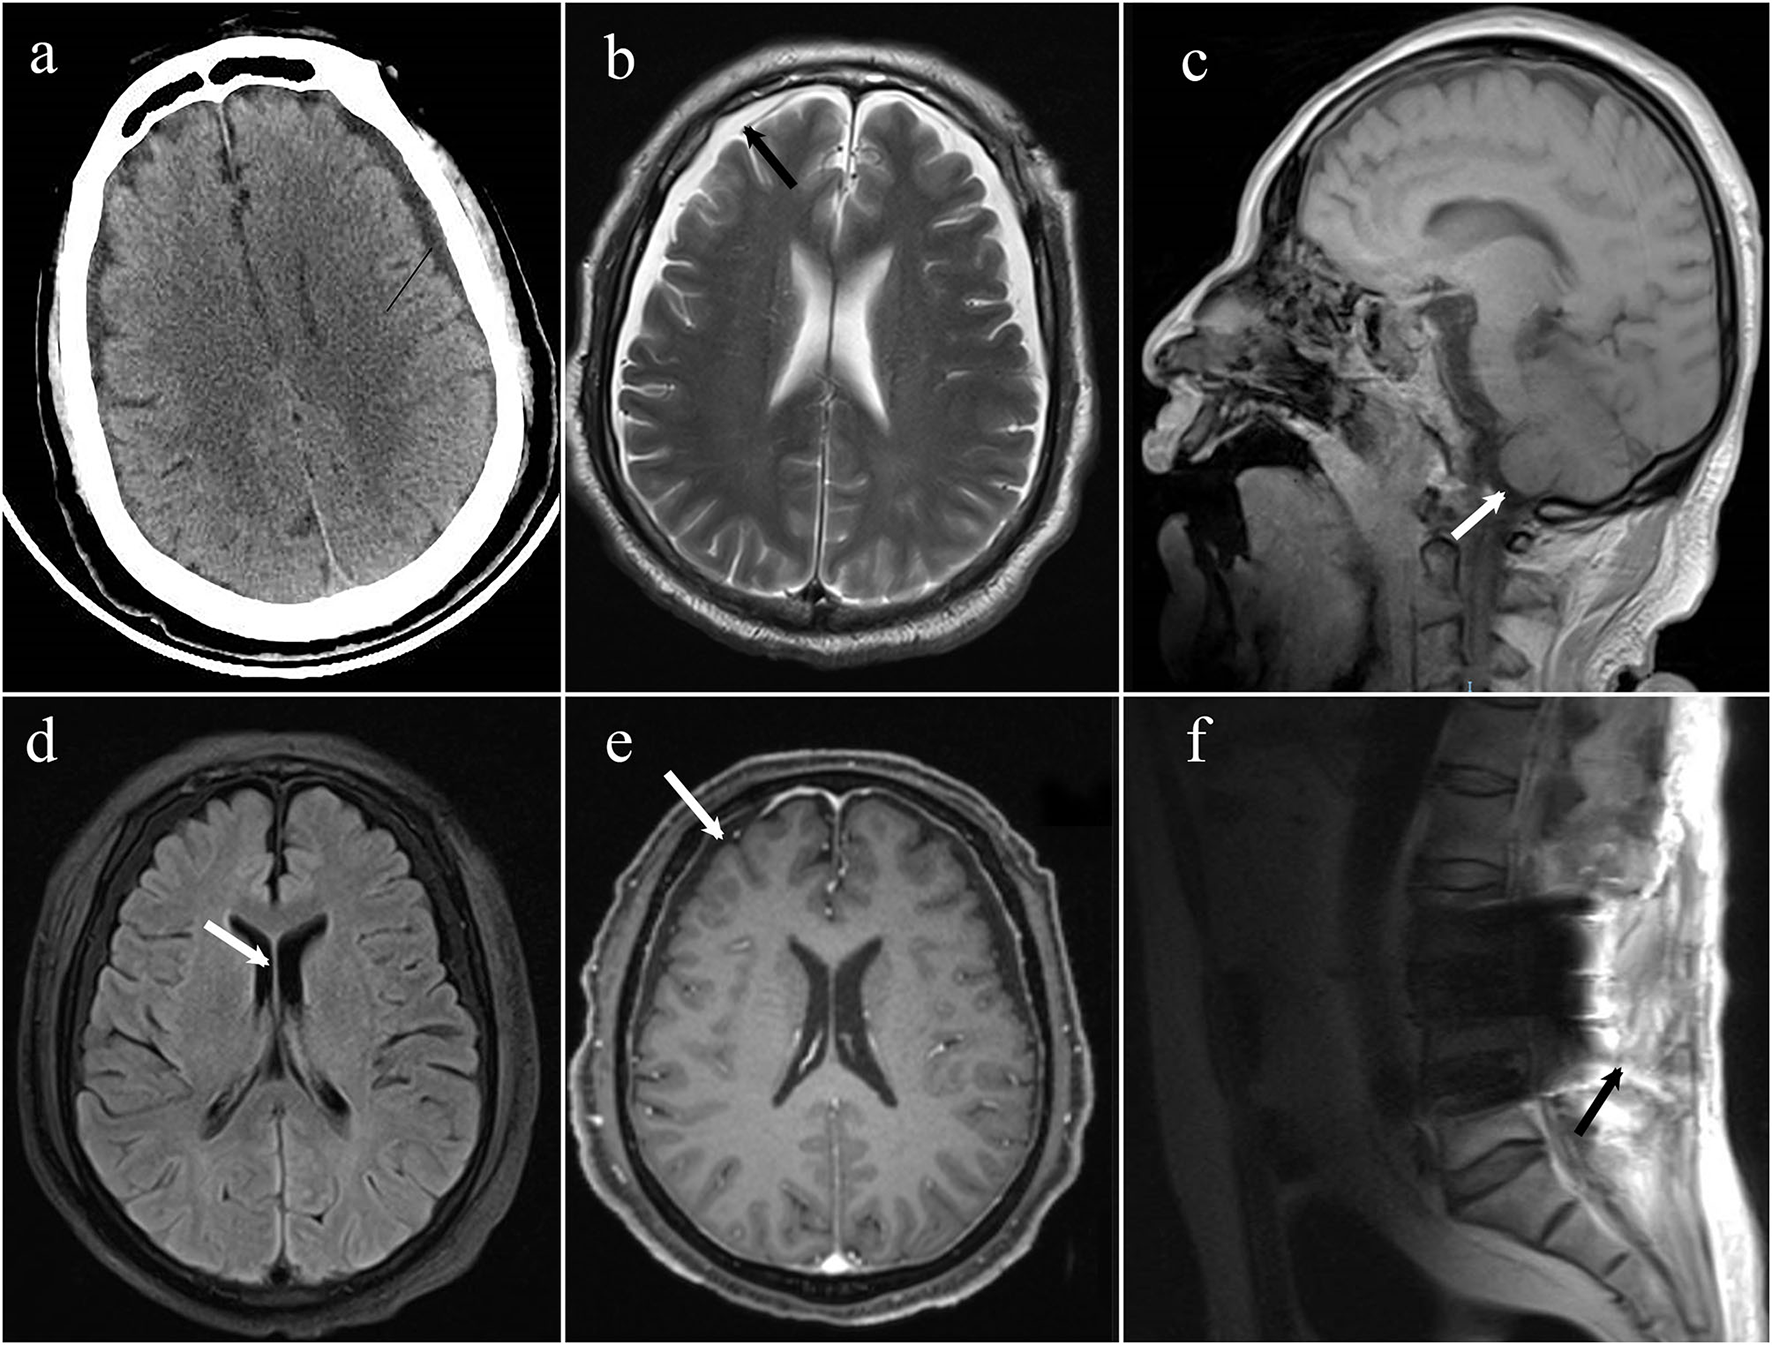

An emergency brain CT (computerized tomography) was conducted, suggesting that the space under the inner plate of the skull was widened on both sides, which was considered a subdural effusion (Figure 1). No obvious signs of cerebral hemorrhage and cerebral infarction were found. After first aid, we conducted target temperature management for the patient and implemented a hypothermia strategy to maintain its core temperature between 32 and 34°C. Levetiracetam and midazolam were added to abort seizures as the disorder of consciousness and seizures persisted. Norepinephrine and dopamine were used to achieve a mean arterial pressure >65 mmHg, with a maximum of 1 μg/kg/min for norepinephrine and 15 μg/kg/min for dopamine. Blood oxygen saturation fluctuated around 85% at pure oxygen concentration due to the presence of refractory hypoxemia. On the second day of ICU admission, he was given a tracheostomy and ventilator-assisted ventilation to maintain oxygen saturation >94% and pCO2 between 35 and 45 mmHg. Given his lack of gastrointestinal hemorrhage and intestinal dysfunction, enteral nutrition was administered within 48 h, along with insulin to keep his blood sugar at 8–10 mmol/L.

Figure 1

(a) The emergency CT suggested that the space under the inner plate of the skull was widened on both sides, which was considered a subdural effusion; (b) axial T2 weighted MRI demonstrates bilateral subdural effusions (arrows); (c) sagittal T1-weighted MRI demonstrates sagging of the brain; (d) axial T1 weighted MRI demonstrates bilateral ventricles narrowing; (e) axial T1 post-gadolinium showing diffuse, mild pachymeningeal thickening, and enhancement (arrow); (f) MRI spine sagittal T2 sequence demonstrates a fluid collection within the posterior paraspinal soft tissue.

On day 10, the patient was successfully removed from the ventilator, so he underwent MRI and enhanced MRI of his brain and spinal cord, revealing evidence of bilateral subdural effusion and mild inferior hernia of the bilateral cerebellar tonsil, bilateral ventricles narrowing, pachymeningeal enhancement, which is consistent with intracranial hypotension. Several tiny hemorrhagic foci were also in the left cerebellar hemisphere and right temporal lobe. Spinal MRI demonstrated postoperative changes of the lumbar spine, lumbosacral fascia edema, and fluid collection between the intrathecal site and the soft tissue; however it did not identify the site of cerebrospinal fluid (CSF) leakage (Figure 2). These changes in the brain were indicative of typical intracranial hypotension, such as subdural effusion, mild inferior hernia of the bilateral cerebellar tonsil, ventricular narrowing, and pachymeningeal enhancement which could be caused by cerebrospinal fluid leakage.